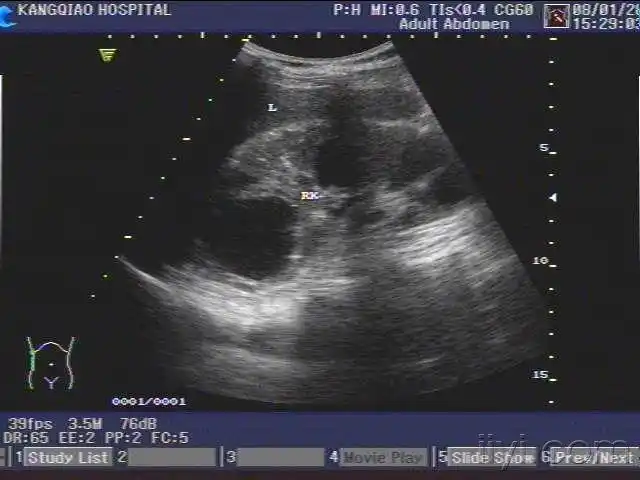

一例多发性肾囊肿在我院超声引导下穿刺成功